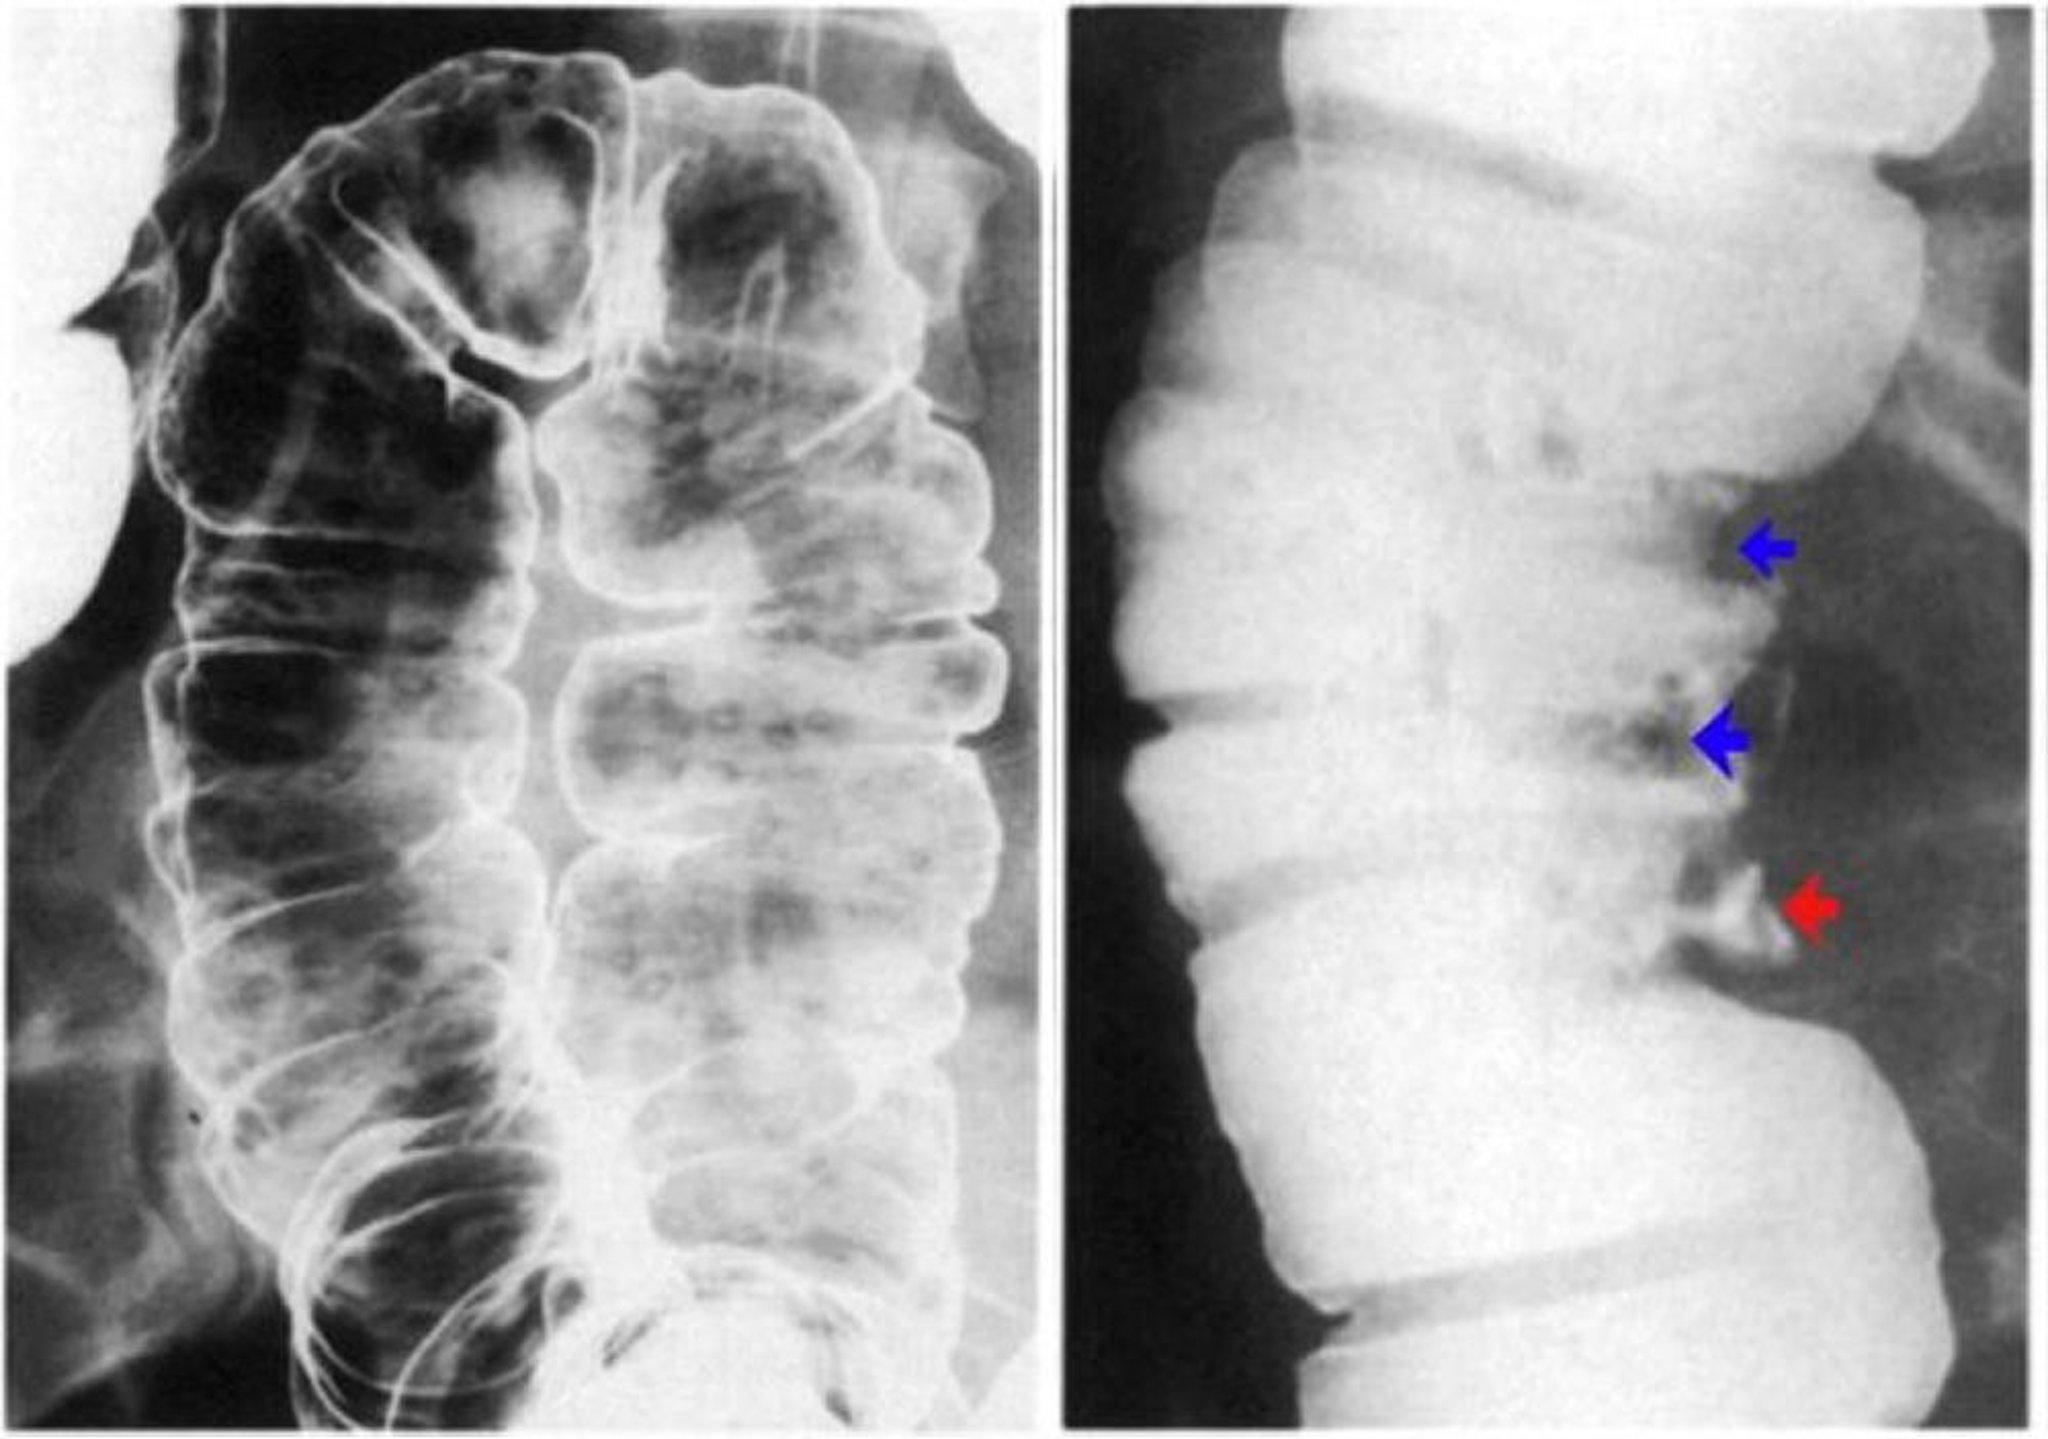

Thuốc xổ bari cho thấy loét thành đại tràng

Hình ảnh bên trái cho thấy vết loét aphthous. Có những vết trợt rời rạc có quầng sáng trên nền niêm mạc bình thường. Hình ảnh bên phải cho thấy giả polyp được biểu hiện bằng các khuyết thuốc cản quang (mũi tên xanh) và vết loét sâu (mũi tên đỏ).